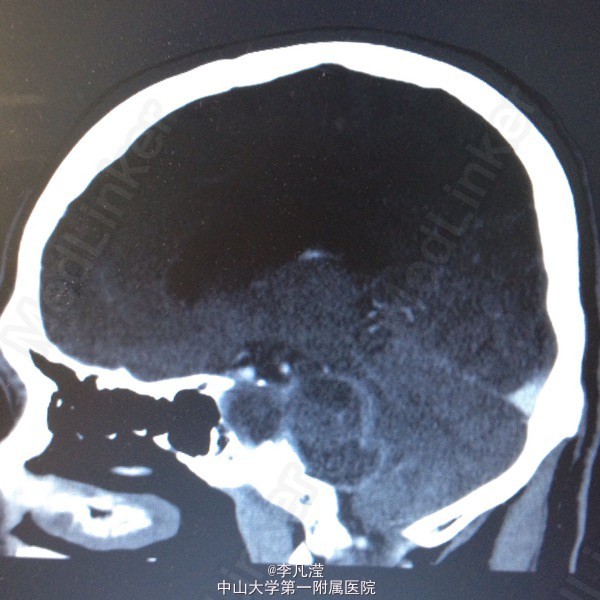

三叉神经鞘瘤一例

右侧中后颅窝底肿块,考虑三叉神经鞘瘤,右侧颞骨岩尖及海绵窦区骨质吸收,右侧麦氏孔扩大,侧脑室及第三脑室轻度积水。